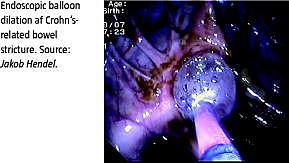

Crohns sygdom er en inflammatorisk tarmsygdom, ved hvilken over 20% af patienterne på trods af optimeret medicinsk behandling udvikler behandlingskrævende stenoser på tarmen. Den eneste behandling har hidtil været kirurgi med tarmresektion eller strikturoplastik. Ved kirurgi er der stor risiko for tilbagefald samt udvikling af adhærence- og korttarmsproblemer. Endoskopisk ballondilatation er udviklet som et alternativ til kirurgi, og efter introduktionen af dobbeltballonenteroskopi (DBE) er tyndtarmen også endoskopisk tilgængelig for diagnostik og terapi. Ved teknikken føres en ballon gennem lumen i det forsnævrede tarmsegment, hvorefter ballonen fyldes gradvist med vand, til den når en diameter på 15 mm. Trykket holdes i et minut. Strikturen udvides derved, og passagen i tarmen genskabes. Ballonen skal række over hele stenosens længde, hvilket begrænser behandlingen til relativt korte stenoser. I det følgende præsenteres vores resultater med metoden.

Fra 2005 til 2011 blev 23 patienter henvist til endoskopisk ballondilatation af tarmstrikturer forårsaget af Crohns sygdom. Disse er alle inkluderet i denne retrospektive opgørelse. Patienterne var i gennemsnit diagnosticeret med sygdommen 13 år forinden (1-34 år). Gennemsnitsalderen var 39 år (20-59 år), og 65% var kvinder. Hovedparten havde fået foretaget tarmresektion inden indgrebet (18/23), heraf hovedparten en ileocækal resektion (12/18). Patienterne havde obstruktive symptomer i form af abdominalia, kvalme eller opkastninger. Patienterne var inden proceduren udredt med tyndtarmspassage, abdominal magnetisk resonans (MR)-skanning og/eller endoskopi. Lokalisation af strikturen afgjorde, hvilket skop der blev anvendt. Således blev et gastroskop benyttet til øvre procedurer, DBE eller spiralenteroskop til stenoser i de orale to tredjedele af tyndtarmen, DBE til den anale tredjedel af tyndtarmen og koloskop til kolon.

I alt 19/23 patienter (82%) fik deres stenose dilateret. Heraf beskrev 17 god effekt (89%). Antallet af dilaterede strikturer pr. session varierede fra en til fem. Årsagen til de fire mislykkede behandlinger var stenosens længde (n = 2), knæk på tarmen pga. adhærencedannelse, samt et tilfælde i hvilket dilatation af stenosen blev vurderet unødvendig under endoskopien. I løbet af en opfølgningsperiode på knap to år (1-43 måneder) oplevede 14/19 recidiv af symptomer (74%). Fem patienter blev henvist til kirurgi (26%), mens resten kunne behandles med fornyet ballondilatation en eller flere gange. Der blev i alt udført 54 dilatationer, hvoraf en resulterede i en komplikation (1,9%) i form af tarmperforation, som medførte akut laparotomi med anlæggelse af stomi. Patienten kunne udskrives efter en uge.